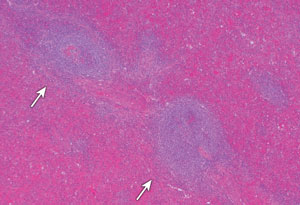

Histological examination of the mass revealed encapsulated lymphoid tissue, with lymphoid foci surrounding central hyalinised vessels. The lymphoid foci were separated by a broad region of erythrocyte-filled sinuses. The appearances were of splenic tissue and there was no evidence of malignancy (Box, C).

C: Histological section of the left hilar mass demonstrating lymphoid foci (arrows) surrounded by splenic red pulp.